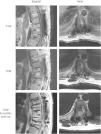

Materials and methodsA literature review of cases of spinal angiolipoma was performed. In addition, two of the cases encountered in our practice are presented. The first case refers to a 35-year-old male patient with a history of spinal fusion because of a T9 fracture, while the second concerns a 46-year-old male patient with an epidural mass extending outside the spinal canal, who underwent fine needle biopsy and embolisation of its feeding vessel.